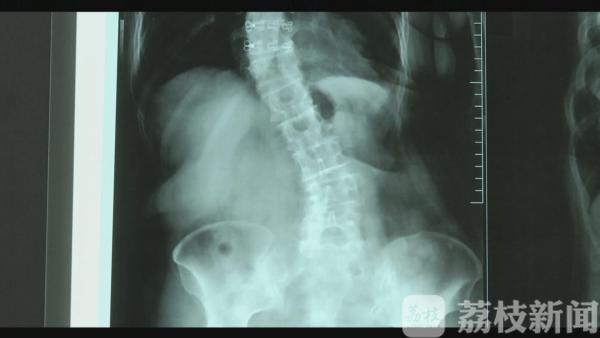

扬州六十多岁的朱阿姨退休后喜欢四处旅游,但是这两年她哪儿都去不了了,因为她的脊椎严重老化,侧弯成了S形,这让她痛苦不已。直到前几天,她接受了最新技术的微创矫正手术,朱阿姨又重新燃起了对生活的热望。

直到前段时间,朱阿姨得知扬大附院正在实施一项矫正脊椎的新技术,便抱着试试看的想法前来诊治。医生经过检查发现,朱阿姨的脊椎之所以弯曲侧突,是脊柱不对称、老化引起的。